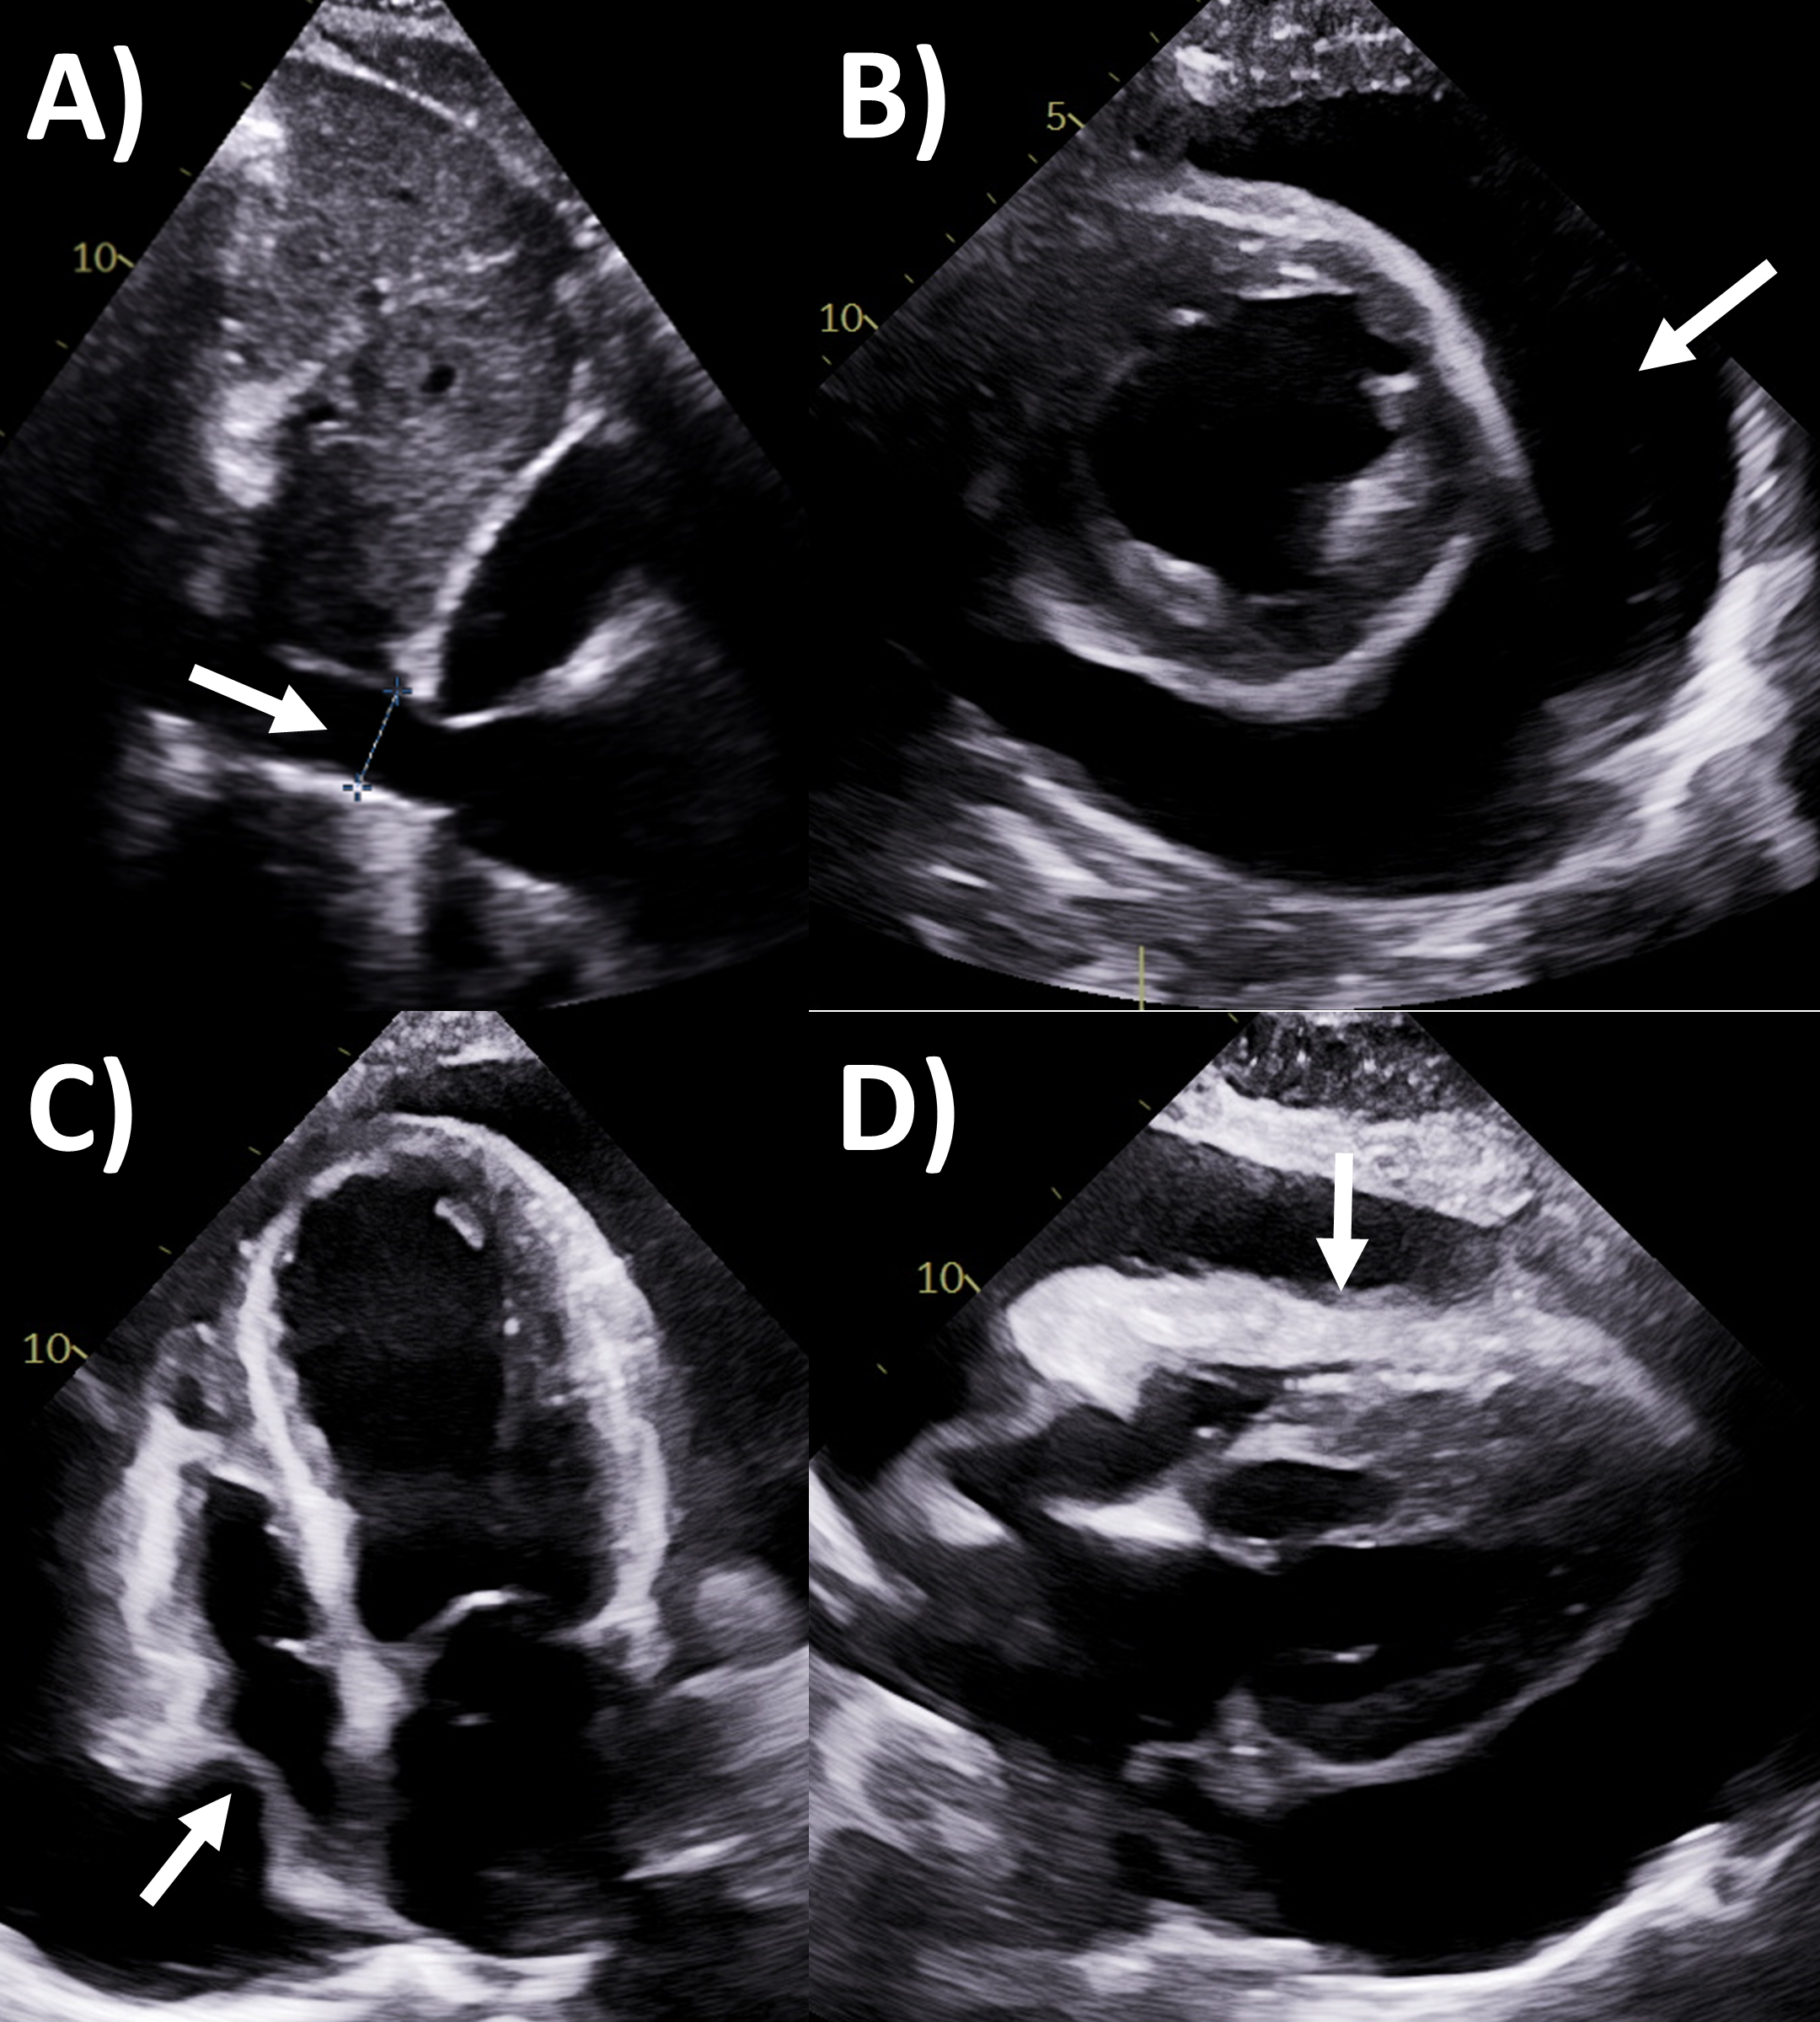

It is critical for cardiology clinicians to be familiar with echocardiographic

features that may be seen in pericardial tamponade, despite it ultimately being a

clinical diagnosis incorporating signs of hemodynamic compromise [2]. The main

echocardiographic criteria according to guidelines (Fig. 2) include dilated

inferior vena cava with minimal (

Fig. 2.Echocardiography evaluation of pericardial tamponade. (A)

Dilated inferior vena cava (2.7 cm) with minimal

Effusive-constrictive pericarditis is an increasingly recognized entity, where both pathological pericardial features (including tamponade) are concurrently present [2]. There is usually a significant pericardial effusion to start with, and the fluid can be organized, echogenic or loculated by echocardiography [2, 28]. The hallmark feature is that after pericardiocentesis is performed to remove the fluid, there is persistently elevated right atrial pressure, right and left ventricular end-diastolic pressures (with dip and plateau waveform) and prior echocardiography characteristics of constriction such as respirophasic septal shift emerge [2, 29].